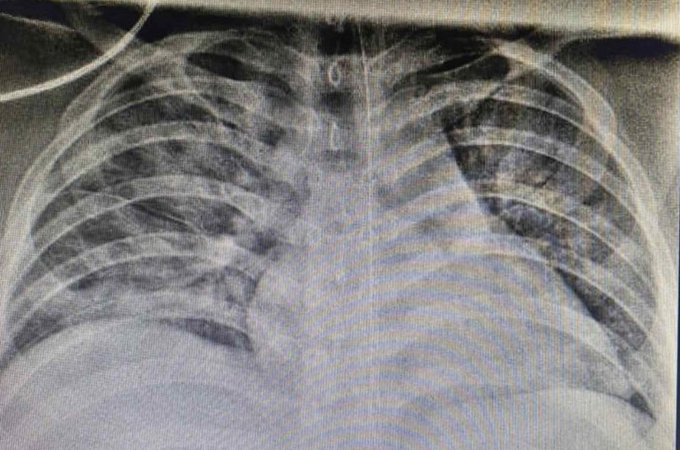

Ảnh chụp X-quang cho thấy phổi bệnh nhi tổn thương nặng cả hai bên do Covid-19. Ảnh: Bệnh viện Nhi đồng Thành phố

Ban đầu SpO2 của bệnh nhi nâng lên 92-93%, sau đó giảm còn 84-86%, tình trạng hô hấp diễn tiến xấu hơn. Trẻ được nâng cấp hỗ trợ oxy thành thở máy không xâm nhập, vẫn không cải thiện. Hình ảnh X-quang phổi cho thấy tổn thương phổi nặng lan tỏa hai bên, biểu hiện hội chứng suy hô hấp cấp tiến triển (ARDS), được đặt nội khí quản thở máy. Bé là bệnh nhi Covid-19 đầu tiên trong cả nước phải đặt nội khí quản thở máy.